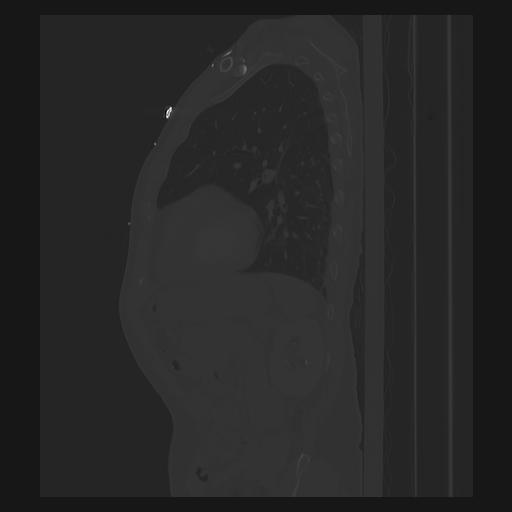

33 PULMON,CE,Sagittal,3.000,PULMON,Sagittal,